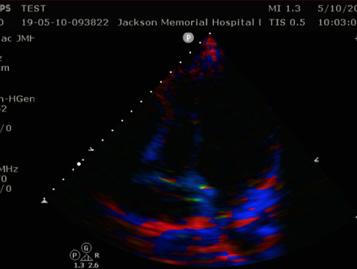

5. Systolic Excursion Velocity (S’) (Fig. 3)

Significance: The S’ is a measure of RV systolic function, and a velocity less than 10 cm/s is suggestive of depressed RV function. Technique: Step 1: Obtain the A4C view. Step 2: Turn on the TDI mode. Step 3: Place the PW Doppler on the lateral free wall near the tricuspid annulus. Step 4: Measure the velocity of the S’ wave.